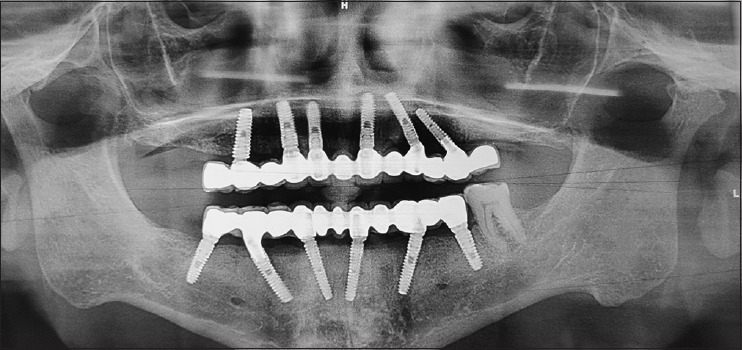

Aim: The aim of this study was to evaluate immediately loaded implants, both clinically and radiographically, in extraction sites (IPIL) and healed sites (HSIL), rehabilitated using All-on-4/All-on-6 protocol, over a time span of 2 years.

Materials and methods: A total of 15 patients were evaluated, in 2 years, for study purpose. Among 87 immediately loaded implants, 44 were IPIL and 43 were HSIL. The bone level was measured using Implant abutment junction as reference point, at 0, 6, 12, 18 and 24 months. Bone loss was calculated as difference of mean.

Results: The average bone loss for 2 years was 1.39 mm and 1.17 mm, in IPIL and HSIL group respectively with 100% implant survival rate and no statistical difference (P < 0.05).

Conclusion: Full arch prostheses can be successfully delivered by immediate loading of implants regardless of placement (healed or extraction sites).